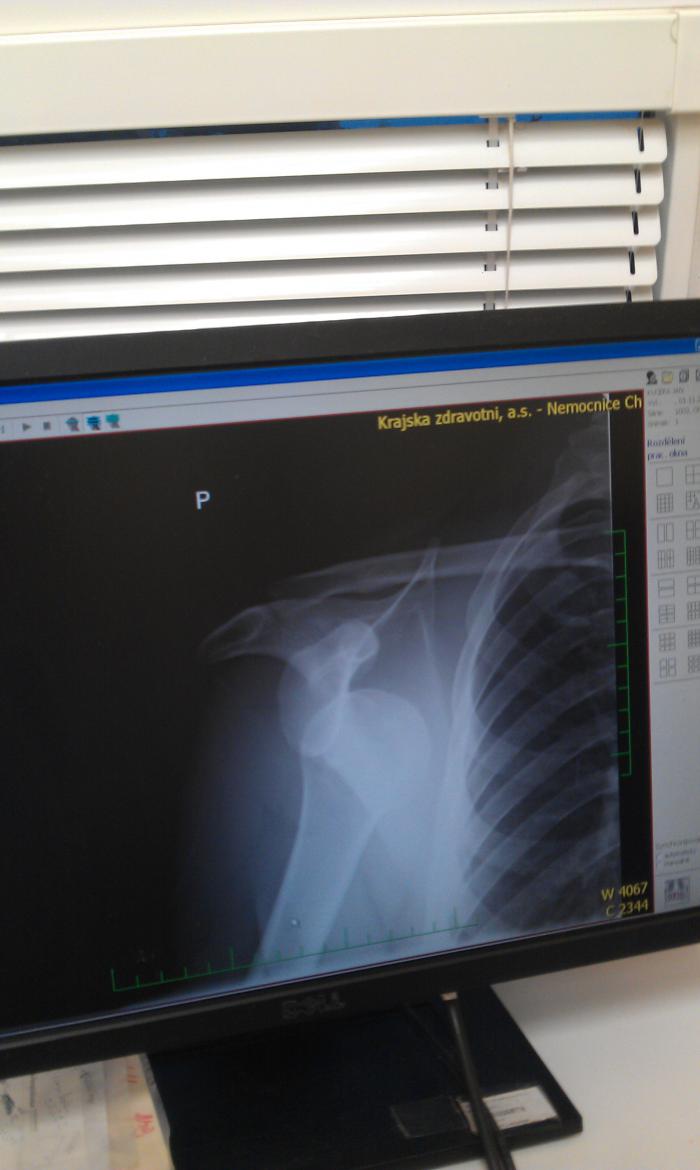

choze Tak novinky:

Jedna noha -nastipnuta kost, pochroumany kotnik, .. - doba leceni cca 14dni az 3tydny

Druha noha- kosti cele, mekke tkane v riti :( komplet sesite vcetne achylovky. Leceni pry 6tydnu pak cca pul roku rehabilitace.

Tohle je aktualni resume.

A nejvic me sere, ze jsem se nekolikrat ptal co je s tou min zranenou nohou a az dneska mi ti koko.i pardon doktori rekli, co tam je.

Od patka maji rentgeny a nikdo z nich nebyl schopnej se na ne poradne podivat.

choze Tak dalsi vykon doktoru!

Houby nastipnuta kost , ale 3 zlomene.

Trosicku se spletly ......